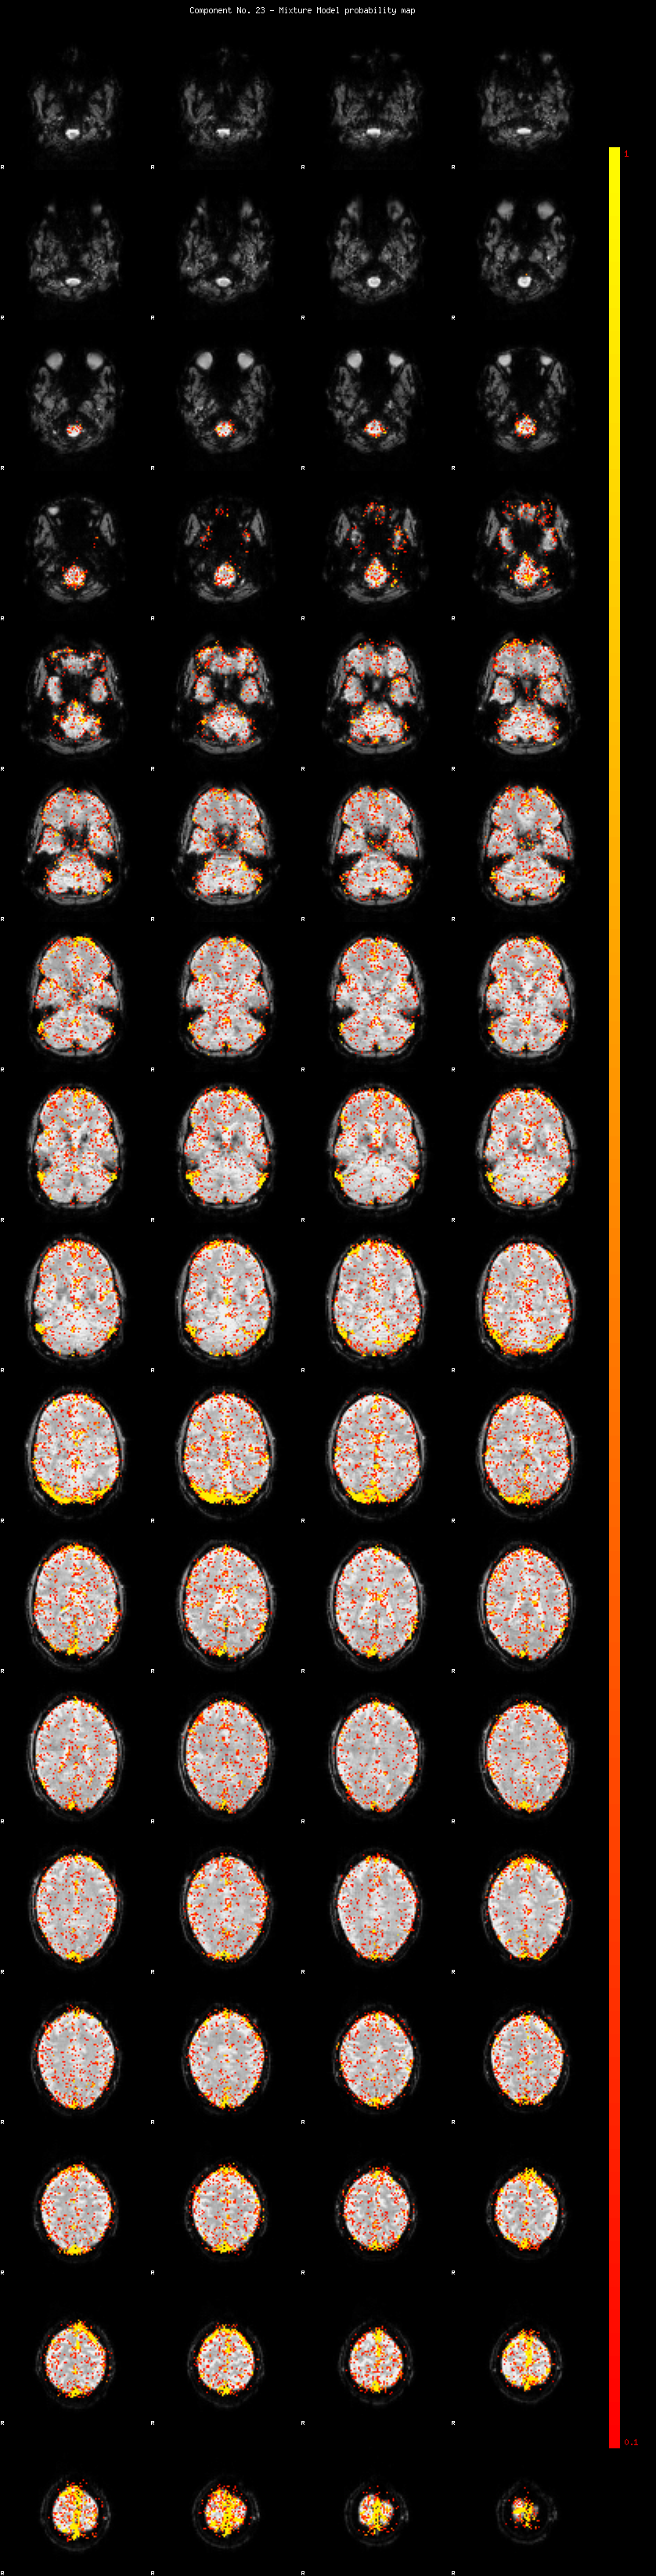

IC_23 Mixture Model fit

Means : -0.000000 3.696606 -2.490361

Vars : 1.000000 6.490062 2.057799

Prop. : 0.906548 0.052257 0.041195